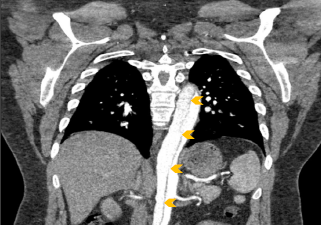

Upon arrival the patient’s blood pressure was 154/79 mmHg. He continued to experience chest and back pain, but was otherwise alert and oriented. His exam was grossly normal, and he reported no numbness or weakness in his extremities. The pre-transfer CT scan was reviewed and a Type A aortic dissection with an intramural hematoma of the ascending aorta and thrombus of the false lumen extending from the aortic arch down to the iliac arteries was confirmed (Figure 2). The patient was taken emergently to the operating room for aortic root repair and aortic valve resuspension with ascending and hemiarch replacement. He was noted to have a normal aortic valve with a primary tear above the sinotubular junction in the ascending aorta that spared the coronary arteries. The root was not enlarged (approximately 3-3.5 cm), and the arch vessels were not dissected. The total cross clamp time was 171 minutes and hypothermia circulatory arrest time was 17 minutes with a lowest temperature of 28 degrees Celsius. The patient was weaned off cardiopulmonary bypass easily and the expected coagulopathy was treated with cryoprecipitate, fresh frozen plasma and platelets. The pericardium was closed partially and two chest tubes were placed. The sternum was closed and the patient was transferred in stable condition and intubated to the surgical intensive care unit (ICU). Approximately 4 hours later he was noted to have decreased bilateral lower extremity blood flow and was taken to the interventional radiology operating room for infrarenal aortic fenestration and aorto-illiac stenting.

Figure 2: Coronal chest CT angiography demonstrating acute aortic dissection (arrows) extending from aortic root (off plane) to iliac arteries (off screen).